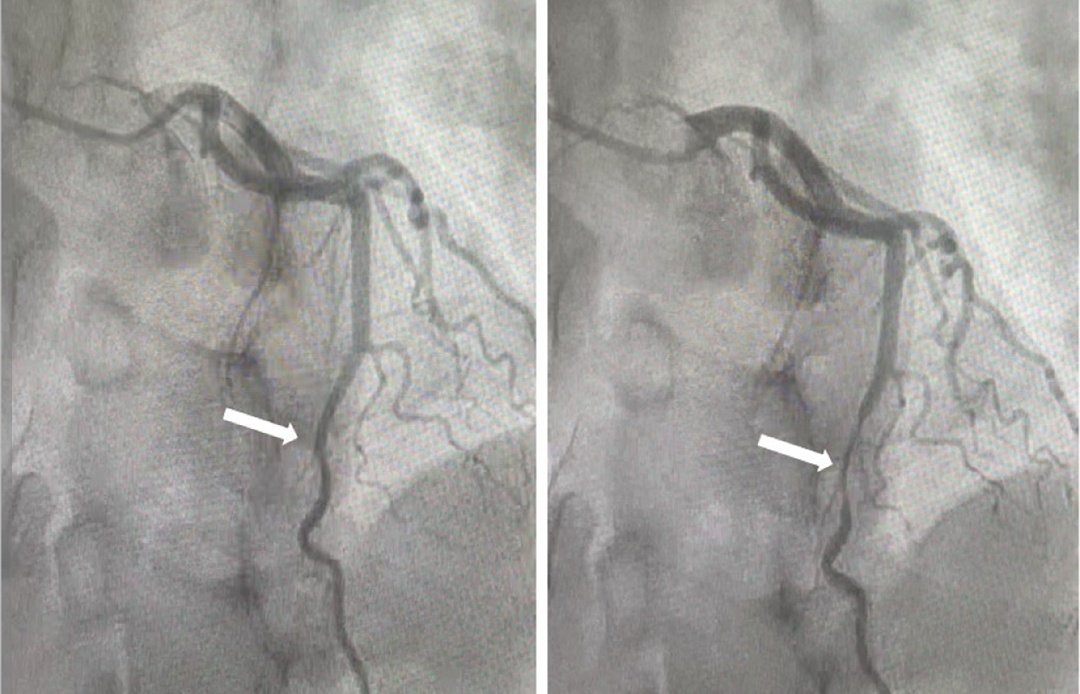

أكد استشاري أمراض القلب الدكتور خالد النمر أن ما يُعرف بـ”جسر القلب” هو حالة يكون فيها جزء من عضلة القلب مغطّيًا للشريان التاجي، وغالبًا الشريان الأمامي، مشيرًا إلى أن انتشاره يصل إلى نحو 20% في الأشعة المقطعية.

وبيّن أن تقييم تأثير “جسر القلب” يحتاج إلى أدلة وظيفية دقيقة، مثل التصوير النووي للقلب أو القياسات الداخلية للشرايين، موضحًا أن هذه الفحوصات تساعد في تحديد ما إذا كان للجسر تأثير فعلي على تدفق الدم.